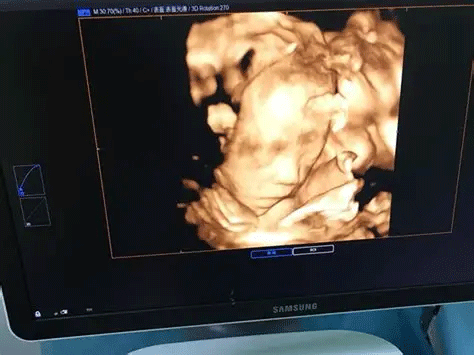

三维彩超,即彩色多普勒超声检查的一种,检查图像呈土黄色,通过多普勒超声仪器发出超声波,对体内各项器官进行成像。三维即其图像是立体的,可以更直观的看到器官的形态,及时发现病变并进行治疗。三维彩超常用于产检,用来判断胎儿的生长发育的情况或是否出现畸形等。

产检中,三维彩超通过测量子宫纵径、子宫体横径、子宫前后径这三条径线来观察胎儿是否正常。以及通过三维立体的成像,可以清晰的显示出胎儿各个内脏器官,以及面部器官、四肢的情况,来简单的判断胎儿是否存在畸形,包括胎儿是否患有先天性心脏病也是能够检查出来的。

24周的胎儿,其身体结构的生长发育已经很完善了,且胎儿大小也很合适,这时候做三维彩超可以很直观的看到胎儿的五官四肢、以及内脏器官,还能了解胎儿双顶径、头围、腹围、股骨长等发育情况。

做三维彩超对胎儿的影响

孕期做的三维彩超检查是通过超声波的传导对胎儿进行检查,是没有辐射的,并通过这种传导再将其形成图像,就能观察到胎儿是否有唇裂、五官或者其他畸形的情况,也能观察出颅脑是否有异常,所以正常情况下三维彩超对胎儿的影响是微乎其微,可以忽略不计的。